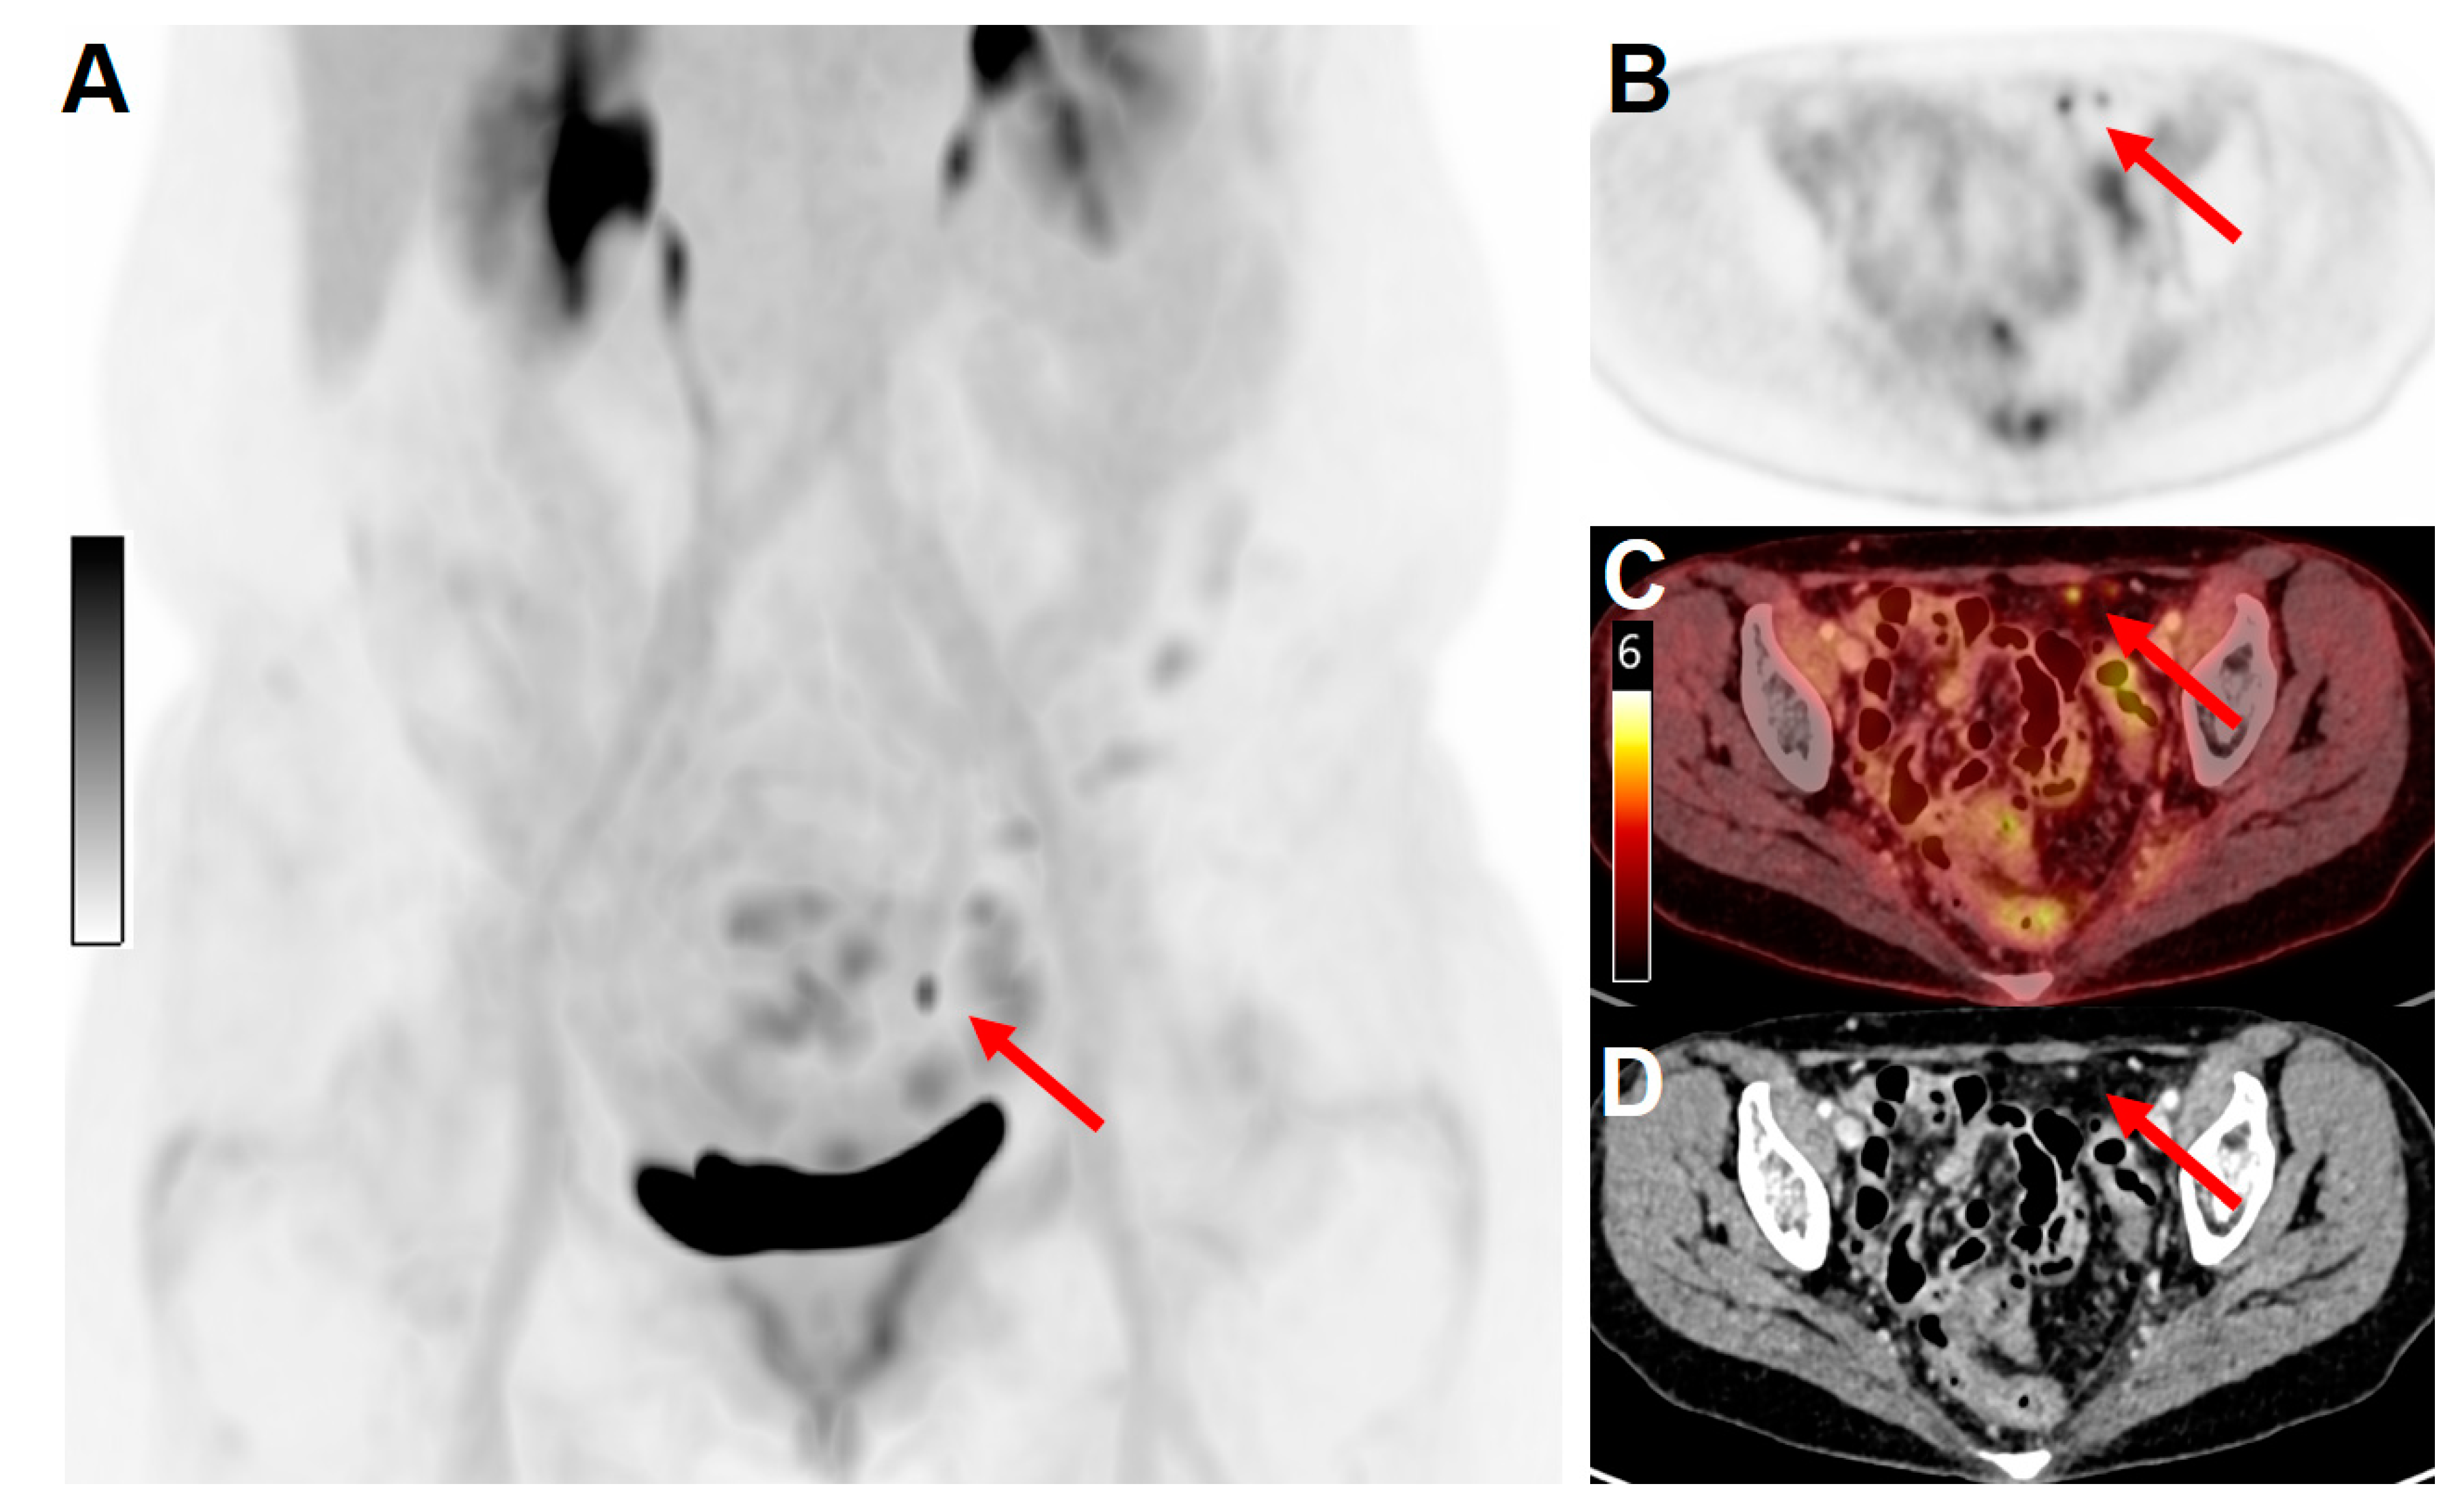

3.3. Detection of Peritoneal Carcinomatosis and Sub-Centimetric Metastases

- higher scanner sensitivity and consequently improved image quality, demonstrating sites of uptake previously unseen on conventional PET that may result in earlier detection of tumor lesions;